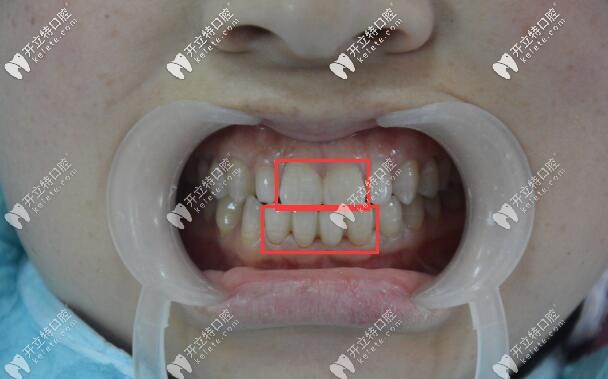

門牙做全瓷牙冠修復(fù)前的照片▲

牙齒情況:先天性牙齒稀疏、牙縫大;要拍結(jié)婚照,嫌前門牙有縫,想要快速改善~

看到這位妹子的牙齒,你是什么反應(yīng)?說實(shí)話,一開始也是建議她做牙齒矯正,但她自己嫌戴牙套的時(shí)間長,想要用瓷貼面來關(guān)閉門牙的縫隙~~~

但是,考慮到下門牙的縫隙較大超過了5MM,做瓷貼面不夠牢固;所以建議做全瓷牙冠(品牌有德國威蘭德和澤康、美國拉瓦、愛爾創(chuàng)),她根據(jù)自己的經(jīng)濟(jì)情況,選擇了國產(chǎn)愛爾創(chuàng)二氧化鋯全瓷牙套。